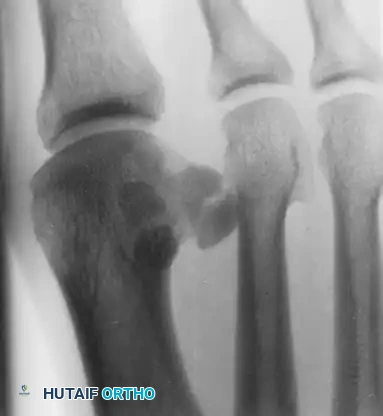

Anteroposterior (AP) and Oblique Views

Standing AP views allow for a comparison of the sesamoids. This is especially helpful if a fracture is suspected but a bipartite sesamoid is present. Accessory sesamoids are normal, although uncommon, findings.

FIGURE 81-100 A: Standing anteroposterior view of both feet on the same cassette allows comparison of sesamoids. This is especially helpful if a fracture is suspected but a bipartite sesamoid is present. Accessory sesamoids (arrows) are normal, although uncommon, findings.